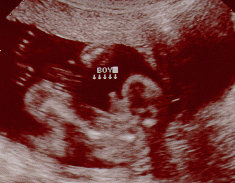

الولد

ولد في الاسبوع ال16